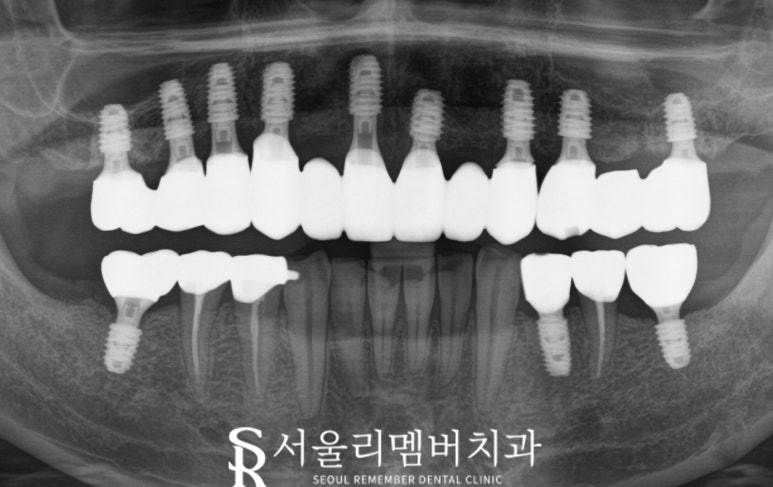

파노라마 x-ray 사진을 먼저 확인해 보면

올바른 교합, 밥을 잘 먹을 수 있는 맞물림으로

위치를 잡고 있는 것을 볼 수 있습니다.

구강 내 사진을 봐도

균형 잡힌 모습으로 바뀌었는데요.

전과 비교해 봐도

너무 많은 변화를 볼 수 있었습니다.